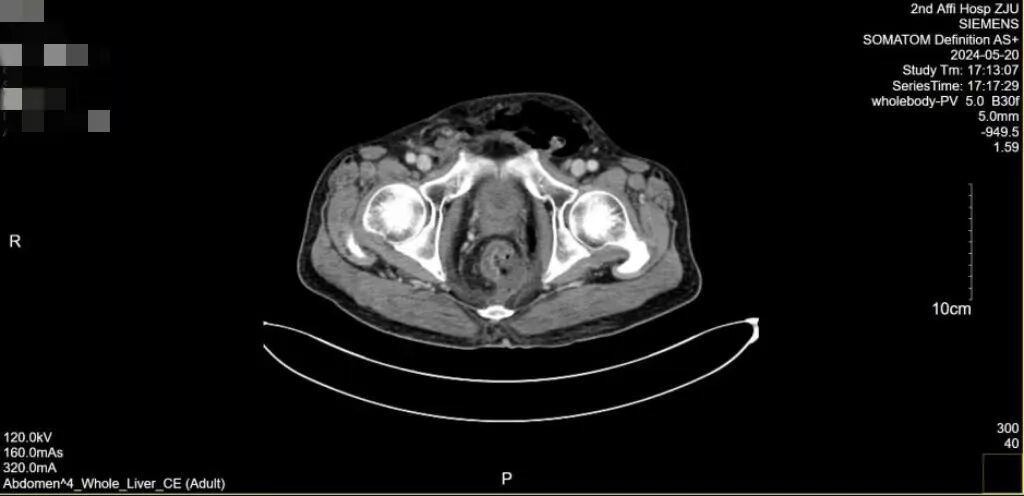

当来到浙江大学医学院附属第二医院急诊时,患者的情况已经相当复杂:全腹 CT 增强扫描提示直肠左侧壁不连续,周围渗出、积液积气,直肠周围筋膜增厚,盆底周围、会阴渗出、积气,两侧腹股沟区、盆壁、左侧腹腔多发积气。

患者腹部 CT 增强扫描报告

查体可见阴囊肛周直至双臀部,大腿根部广泛红肿,阴囊阴茎高度肿胀。